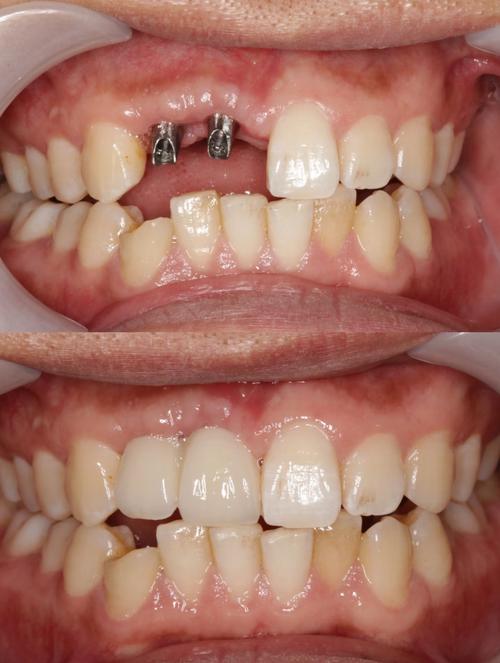

种植牙种太深的危害不容忽视,最直接的是对邻近解剖结构的损伤:当下颌后牙区种植体过深时,可能压迫或损伤下牙槽神经,导致下唇、颏部麻木、感觉异常,严重者可出现持续性疼痛;上颌后牙区种植体若穿透上颌窦黏膜,可能引发上颌窦炎,表现为鼻塞、流脓、面部胀痛,甚至导致种植体周围感染,种植体位置过深会影响修复效果:种植体平台低于牙槽嵴顶过多,会导致基台连接困难,修复体高度不足,影响咬合功能;牙龈组织因缺乏足够支撑可能出现萎缩,影响美观,远期来看,种植体过深还可能因周围血供差、应力集中等问题,增加种植体周围炎、骨吸收甚至种植体松动的风险。

针对种植牙种太深,处理方法需根据具体情况选择,若术中即时发现,且种植体位置偏差较小,可通过调整基台角度或使用个性化基台补救;若已侵入重要结构(如下颌管、上颌窦),需及时取出种植体,待骨愈合后重新植入,术后若出现神经损伤,可给予甲钴胺、维生素B族等营养神经药物,多数患者在3-6个月内可逐渐恢复;若合并上颌窦炎,需进行抗感染治疗,必要时行上颌窦修补术,对于修复期患者,可通过牙龈成形术、临时冠引导牙龈塑形等方式改善美观,若咬合问题严重,可能需拆除修复体重新制作。